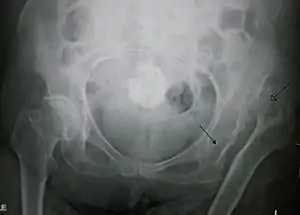

![]() | |

| Congenital dislocation of the left hip in an elderly person. Closed arrow marks the acetabulum, open arrow the femoral head. | |

If the joint is fully dislocated a false acetabulum often forms (often higher up on the pelvis) opposite the dislocated femoral head position.